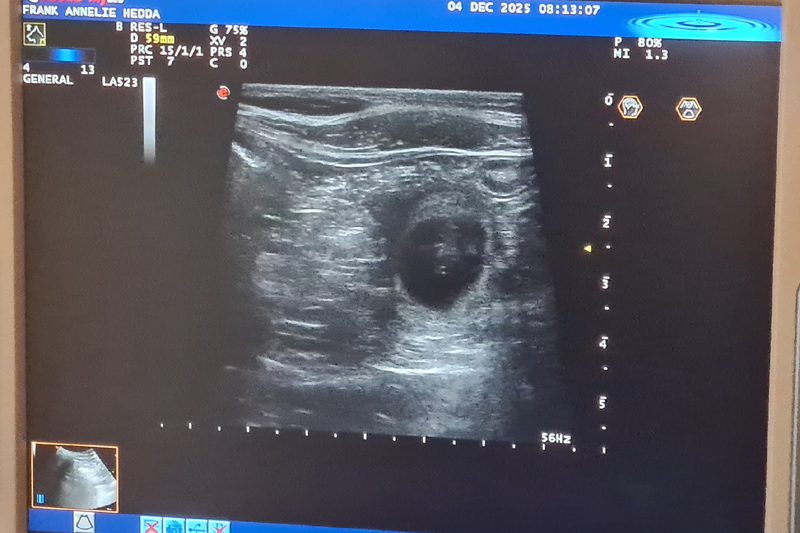

Ultraljud på måndag

På måndag gör vi ultraljud för att se om Fanny har valpar i magen. Håll tummarna!